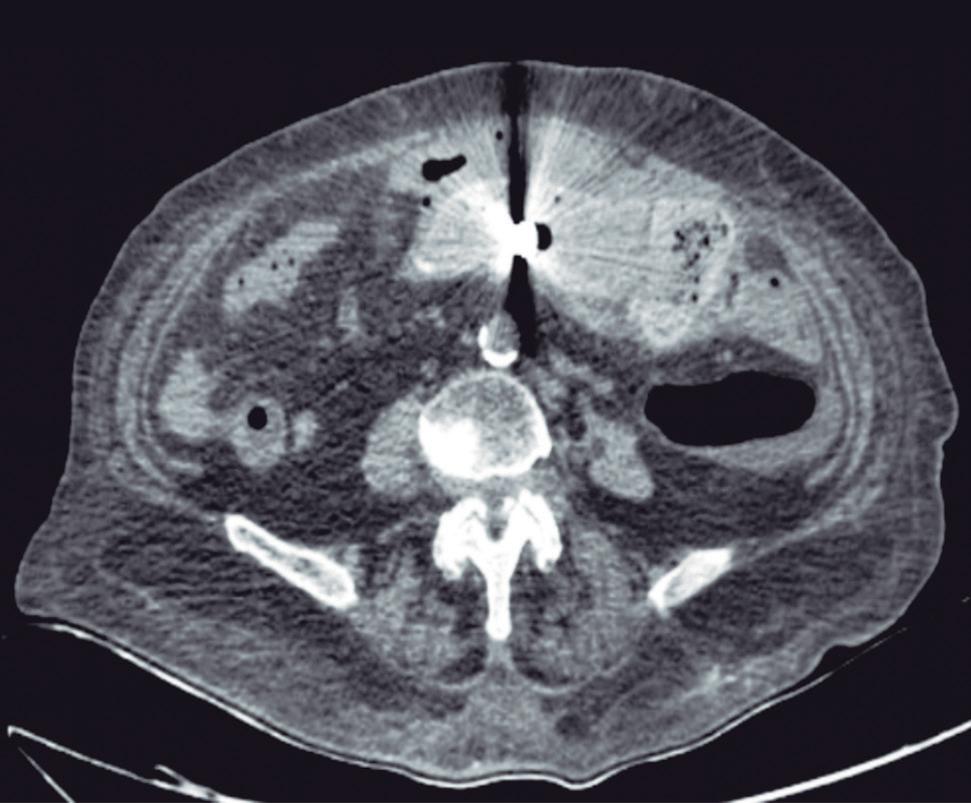

Evaluación endoscópica e histológica

La endoscopía superior es un procedimiento fundamental para el diagnóstico, la evaluación de la respuesta al tratamiento y el monitoreo a largo plazo de la actividad de la EEo. Los hallazgos endoscópicos típicos incluyen edema (reducción de vascularidad), anillos esofágicos fijos, exudados blancos, surcos longitudinales, estenosis, estrechamiento de la luz esofágica, friabilidad de la mucosa (mucosa en papel crepé) y una consistencia firme de la mucosa al realizar biopsias (signo de “tracción" o "resistencia”) en pacientes con fibrosis (Figura 1). Estos hallazgos no son patognomónicos y no constituyen un criterio diagnóstico; sin embargo, cuando se evalúa de forma cuidadosa, en la gran mayoría de los casos se pueden observar.19-21

En el panel A se observa un esófago con edema difuso y pliegues longitudinales; en el panel B se aprecia edema con pliegues y exudados blanquecinos; en el panel C se evidencia un estrechamiento luminal acompañado de anillos esofágicos y exudados; y en el panel D se muestra un desgarro mucoso posterior a la dilatación con bujía de Savary, hallazgo esperado tras este procedimiento terapéutico.

Figura 1. Características endoscópicas de la esofagitis eosinofílica